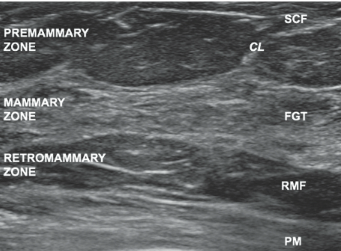

Breast tissue layers

1. Premammary

- Superficial: skin → ant mammary fascia

- Skin (epidermis + dermis), subcutaneous fat, coopers ligaments

- Lesions: usually not true breast lesions (e.g. lipoma, subcutaneous cyst)

2. Mammary

- Middle: ant mammary fascia → post mammary fascia

- Lobes, ducts, interlobular stroma

- Where most breast lesions arise

3. Retromammary

- Deep: post mammary fascia → chest wall

- Fatty tissue, coopers ligaments

- Best seen with mamms (US = not well seen - compression against chest wall)